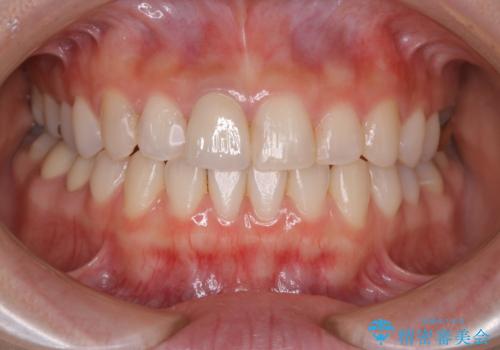

- 前歯一本だけ色が暗いことが気になりご相談にいらした患者様です。周辺の歯と色味をぴったり合わせることで自然な仕上がりになりました。

自費診療で用いられる材料は保険適応の材料に比べて、より精密で適合の良い被せ物作ることができるため、長期的な虫歯のリスクを大幅に減らすことが可能です。